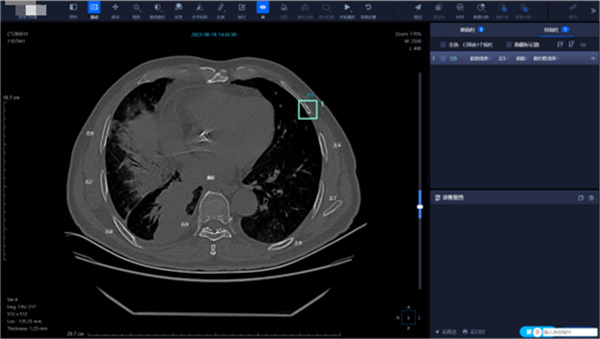

(2)AI辅助诊断肺结节应用界面